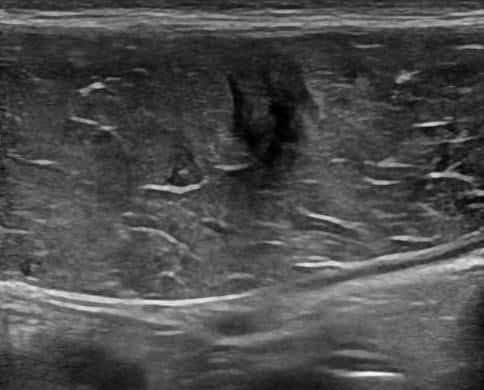

Chấn thương thành bụng

» Thông tin: Nam giới – 18 tuổi.

» Lâm sàng: Chấn thương thành bụng.

# Đụng dập, tụ máu cơ thành bụng.